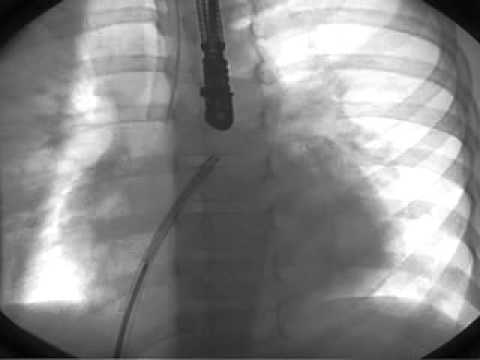

Transcatheter Closure - Movie 1: PDA-R sequence